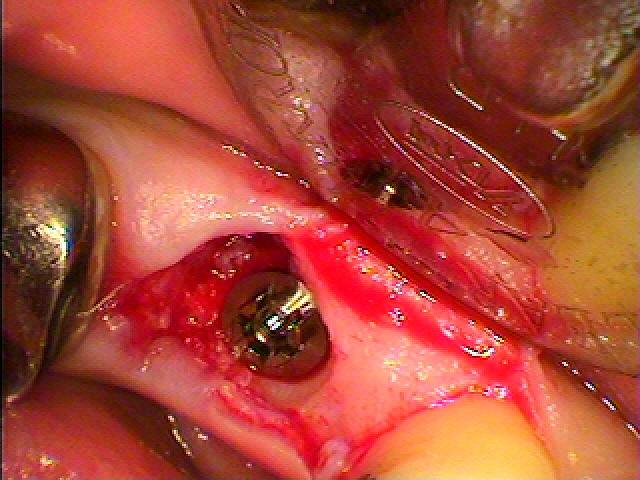

左下の奥歯のインプラント埋入|お知らせ |広島市安佐南区の歯科医院 左下の奥歯のインプラント埋入 トップ お知らせ・ブログ お知らせ 左下の奥歯のインプラント埋入 左下の奥歯のインプラント埋入 左下の6番ヘミセクション このクラウンが揺れてきました 骨吸収が認められます 割れているため抜歯となりました 抜歯しました 埋入していきました 補填材を入れ縫合して終了です このように埋入しています Web診療予約 初めての方へ 選ばれ続ける理由 院内設備について 歯が痛いしみる一般歯科 歯がぐらぐらする歯周病 健康な歯を保ちたい予防歯科 子供の虫歯予防をしたい小児歯科 銀歯をセラミックに審美歯科 白い歯を目指しませんか?ホワイトニング 矯正専門医がいるので安心矯正歯科 抜けた歯を補いたいインプラント・入れ歯 医院案内 スタッフ紹介 メリィハウス歯科クリニックオフィシャルホームページ ラベンダー歯科クリニックオフィシャルホームページ お知らせ・ブログ ホーム 診療科目 一般歯科 歯周病治療 予防治療 小児歯科 審美治療 ホワイトニング 矯正歯科 入れ歯・インプラント マウスピース矯正 初めての方へ 院長・スタッフ 設備紹介 医院案内・アクセス メニューを閉じる